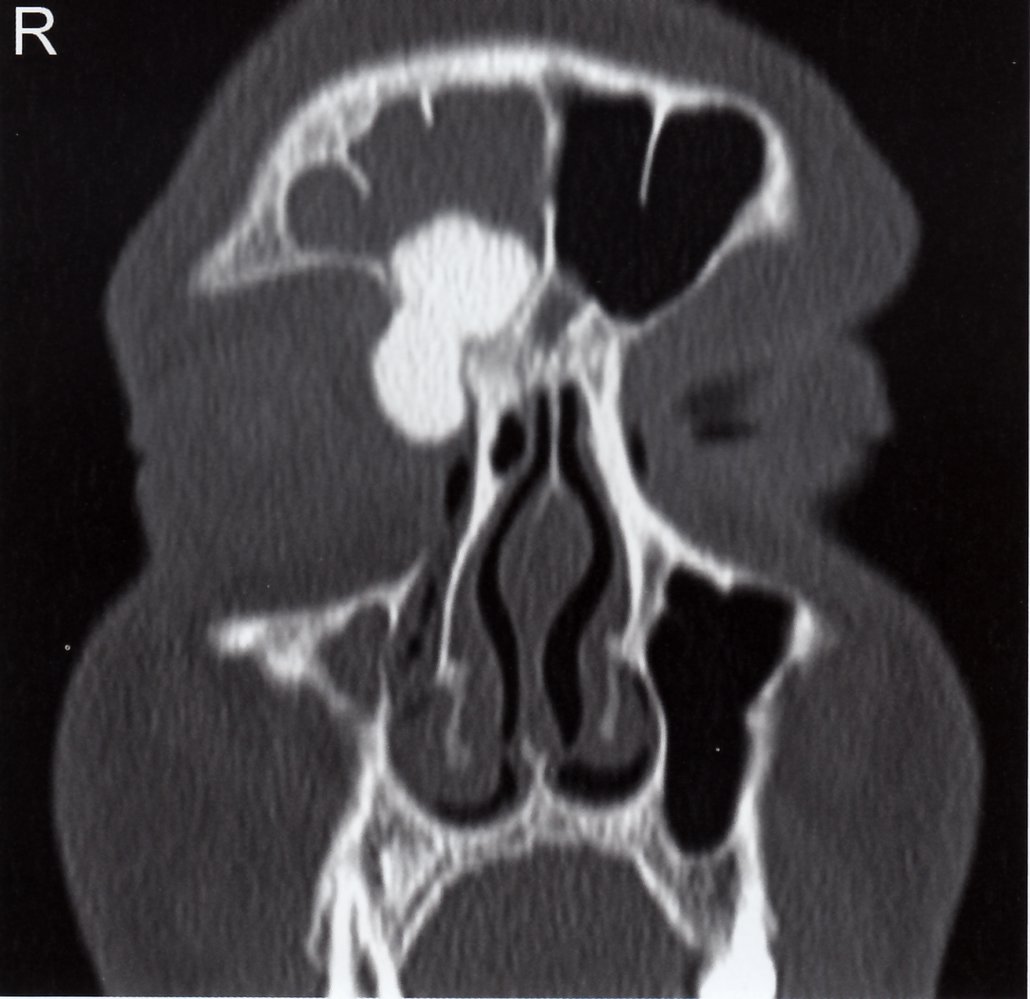

• Description: : a rare disorder caused by clonal proliferation of Langerhans cells (antigen-presenting cells) [11]

• Epidemiology: : peak incidence between 5 and 10 years

• Clinical features

• Osseous lesions (90%): pain and/or swelling, pathological fractures

• Localization: skull (most common site), femur, vertebra, mandible, ilium, ribs

• Can cause recurrent otitis media if the mastoid bone is involved

• Diagnostics

• Normal calcium levels

• X-ray: osteolytic lesions with or without marginal sclerosis

• Biopsy (confirmatory test): proliferation of Langerhans cells (polygonal cells with coffee bean-shapednucleiand eosinophilic cytoplasm) ; [12][13]

• Electron microscopy: Birbeck granules (tennis racket-shaped or rod-like structures) in the cytoplasm

• Immunohistochemistry: cells are positive for S100, CD1a, and/or CD207

• Treatment

• Solitary bone lesions in low-risk anatomical regions

• Asymptomatic lesion: a wait-and-watch approach may be appropriate

• Symptomatic lesion: curettage and/or excision (as a part of biopsy)

• Bone lesions in high-risk anatomical regions (e.g., lesions involving the odontoid process or regions of the skull other than the vault), multifocal bone involvement, or systemic manifestation: vinblastine and prednisone